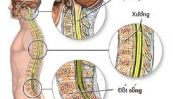

Viêm tủy cắt ngang là tình trạng viêm ở cả hai bên của một phần tủy sống, thường làm hỏng vật liệu cách điện bao gồm các sợi tế bào thần kinh (myelin). Vậy nguyên nhân và triệu chứng của bệnh là gì? Làm thế nào để điều trị và phòng ngừa bệnh hiệu quả? Tham khảo bài viết dưới đây để hiểu rõ hơn nhé!